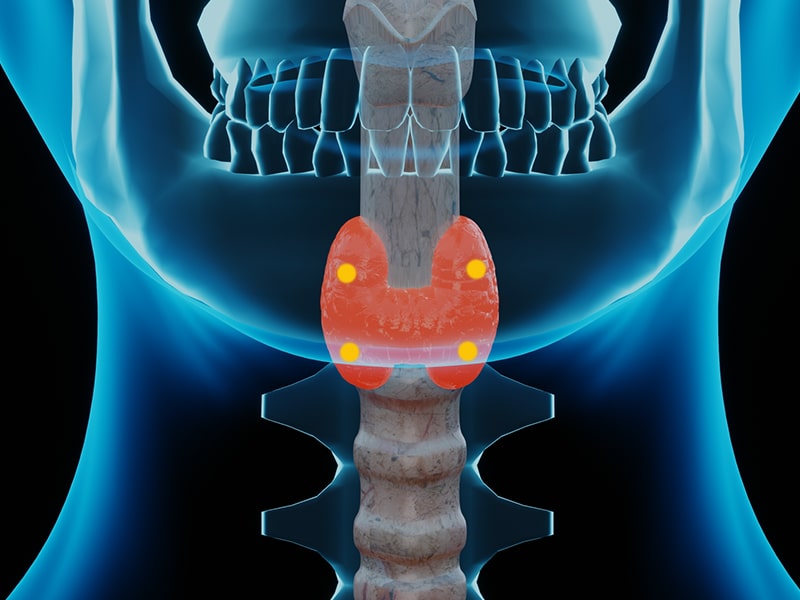

Tiroid ve paratiroid bezleri fiziksel olarak birbirine yakın olmalarına ve vücudun endokrin sisteminin bir parçası olmalarına rağmen, işlevleri birbiriyle ilgisizdir. Paratiroit bezi, tiroid bezinin yakınında tipik olarak dört tanedir. Her paratiroid bezi normalde yaklaşık bir pirinç tanesi (yaklaşık 3-5 milimetre çapında ve 30 - 60 miligram ağırlığında) büyüklüğündedir. Paratiroid bezleri, kan dolaşımındaki kalsiyum seviyelerini kontrol eden paratiroid hormonunu (PTH) salgılar. Vücudun diğer bölgeleri, özellikle kemikler, böbrekler ve ince bağırsak, kandaki kalsiyum seviyelerini artırarak paratiroid hormonu PTH'ye yanıt verir.

Paratiroid bezi hastalıkları nelerdir? Paratiroid bezlerinin fazla paratiroid hormonu (PTH) salgılaması ya da az PTH salgılamasına göre paratiroid hastalıkları farklılık göstermektedir. Paratiroid hormonu (PTH) , vücutta kalsiyumunun çoğunun depoladığı böbrek ve kemiğin doğrudan etkileyerek kandaki kalsiyum seviyesini düzenler. Hiperparatiroid Paratiroid bezleri çok fazla paratiroid hormonu (PTH) ürettiğinde ortaya çıkan durumdur. Hiperparatiroidizm sonucunda kan kalsiyum düzeyi yükselir. Hiperparatiroidizm farklı nedenlerle ortaya çıkabilmektedir. Hiperparatiroidizm nedenine göre tedavi şekli de değişmektedir. Primer hiperparatiroidizmde, bir veya daha fazla paratiroid bezinin büyümesi, paratiroit hormonunun aşırı üretimine neden olur. Primer hiperparatiroidizmin tedavisi genellikle cerrahi yöntemlerdir. Primer hiperparatiroidizm kan kalsiyum yüksekliğinin en sık nedenleri arasındadır. Kadınlarda daha sık görülür. Hipoparatiroid Hipoparatiroidizm, vücudun anormal derecede düşük paratiroid hormonu (PTH) ürettiği nadir bir durumdur. Kandaki kalsiyum düzeyi düşerken, fosfor değerleri artış göstermektedir. Hipoparatiroidizm tedavisi, kalsiyum ve fosfor seviyelerini eski haline getirmek için genellikle ömür boyu takviye almayı içerir. Paratiroid bezi kanseri Çok nadir görülen bir kanser türüdür. Genellikle yüksek paratiroid hormonu (PTH) seviyeleri ile birlikte görülmektedir.